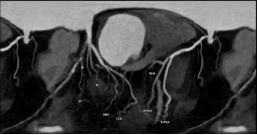

冠脉 CTA 检查是排查心脏隐患、防范猝死风险的重要手段,也是我们了解自身心脏状况的便捷选择。

检查后,很快就能出具影像诊断结果,清晰呈现心脏血管真实状况,能让隐患无所遁形。

通过冠脉 CTA,能清晰地看出多种心脏相关疾病:

最常见的是冠状动脉粥样硬化,也就是常说的「血管变窄」;

还能发现血管内的斑块,判断斑块的大小和稳定性,预警心肌梗死;

还能排查冠脉畸形、血管闭塞等,为临床治疗提供精准依据。